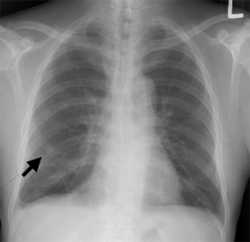

흉부 단순촬영(X-ray), 복부골반 전산화단층촬영(CT), 자기공명영상(MRI), 뼈동위원소검사(Bone scan)를 이용하게 됩니다. 국소 연부조직의 침윤과 림프절의 전이 여부는 전산화단층촬영(CT) 혹은 자기공명영상(MRI)을 통해 진단하고, 특히 요도암에 의한 음경 해면체의 침윤을 확인하는 데는 자기공명영상(MRI)가 유용합니다. 그 외 요도암의 국소 진행으로 직장의 침윤이 의심되는 경우에는 에스결장 내시경을 시행할 수 있습니다. 상부요로를 평가하기 위해서는 경정맥 신우조영술(IVP)을 시행합니다.

암의 전이로 의심되는 폐 병변이 관찰됩니다.

[ 암의 전이로 의심되는 흉부 X-ray 검사 ]